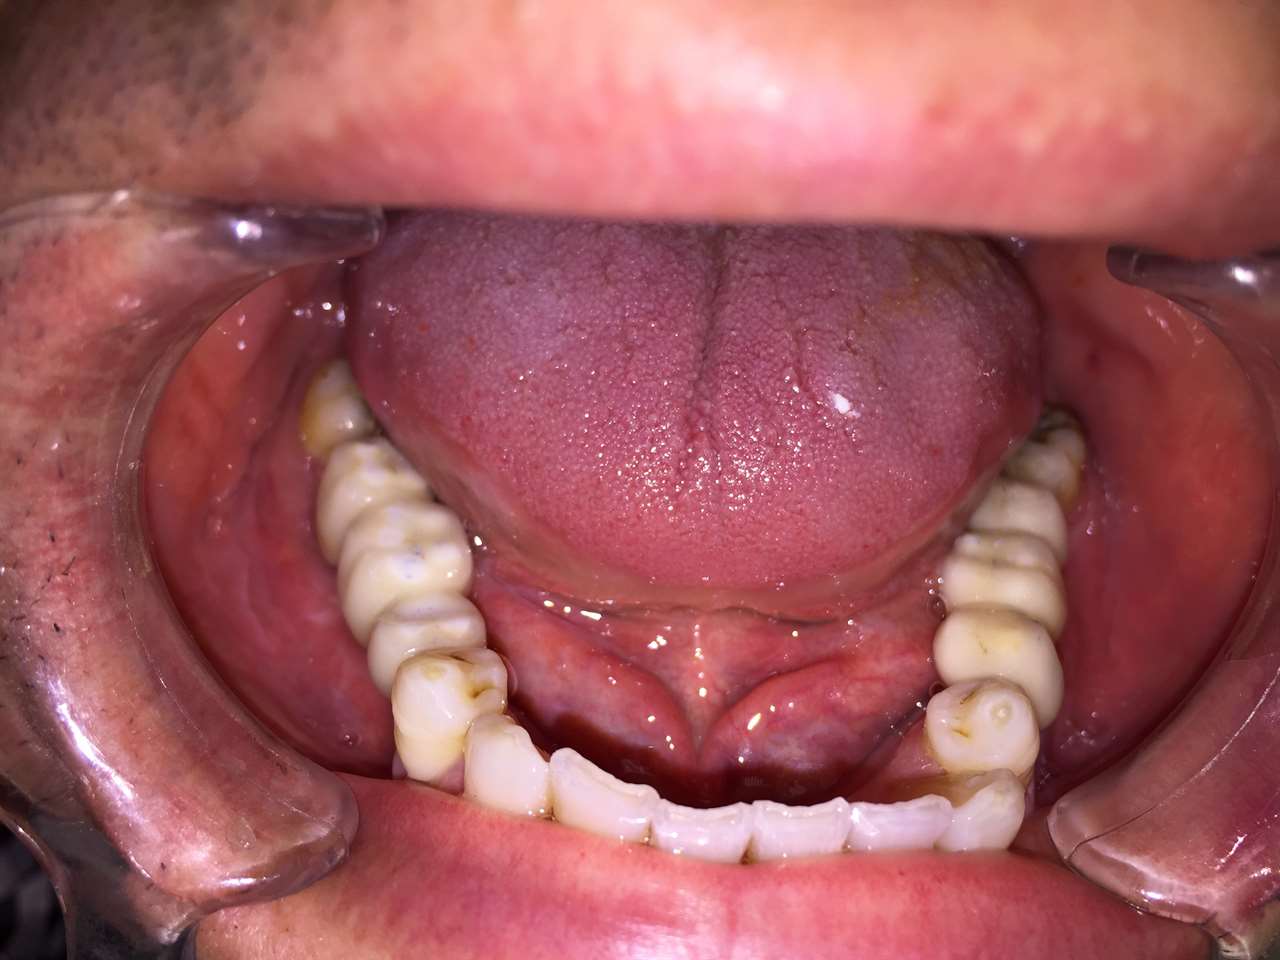

Teljes fogatlanság helyreállítása 2 nap alatt

Teljes fogatlanság helyreállítása 2 nap alatt azonnal terhelhető svájci IHDE implantátumokkal és PMMA műanyag hidakkal. Intraorális szkennerrel vettünk lenyomatot az implantáció után, és erre a digitális mintára készítette el a fogtechnika a hidak digitális tervezését, majd faragta ki műanyagból. Ezt a gyors munkát az azonnal terhelhető implantátumok és a digitális lenyomat, tervezés segítségével tudtuk megcsinálni mindössze 2 nap alatt. Dr. Kelemen Péter és a Symbion Fogtechnika munkája.